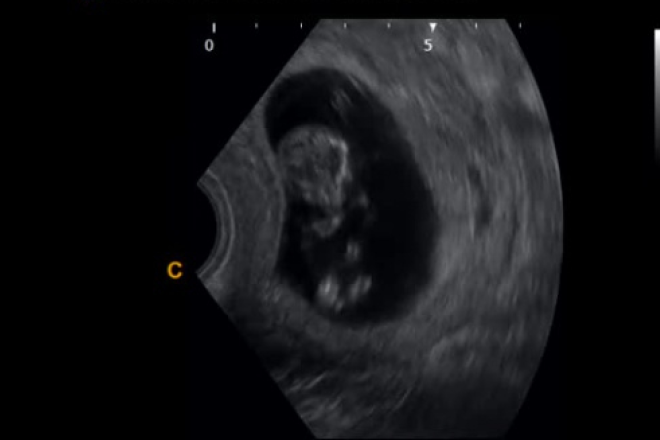

Perfil biofísico para conocer el bienestar fetal

Se le denomina técnica de valoración del bienestar fetal de Manning, y sus parámetros son: frecuencia cardíaca fetal, movimientos respiratorios, movimientos fetales, tono fetal, líquido amniótico (Manning), grado placentario (Vintzileos).

MOVIMIENTOS CORPORALES Y TONO FETAL: Los movimientos corporales fetales son resultado de la estimulación de la placa neuromuscular en el músculo esquelético., Los movimientos fetales pueden identificarse en los humanos a las seis semanas de gestación, ultrasonido de tiempo real, doppler y registro de percepciones hecho por la paciente.